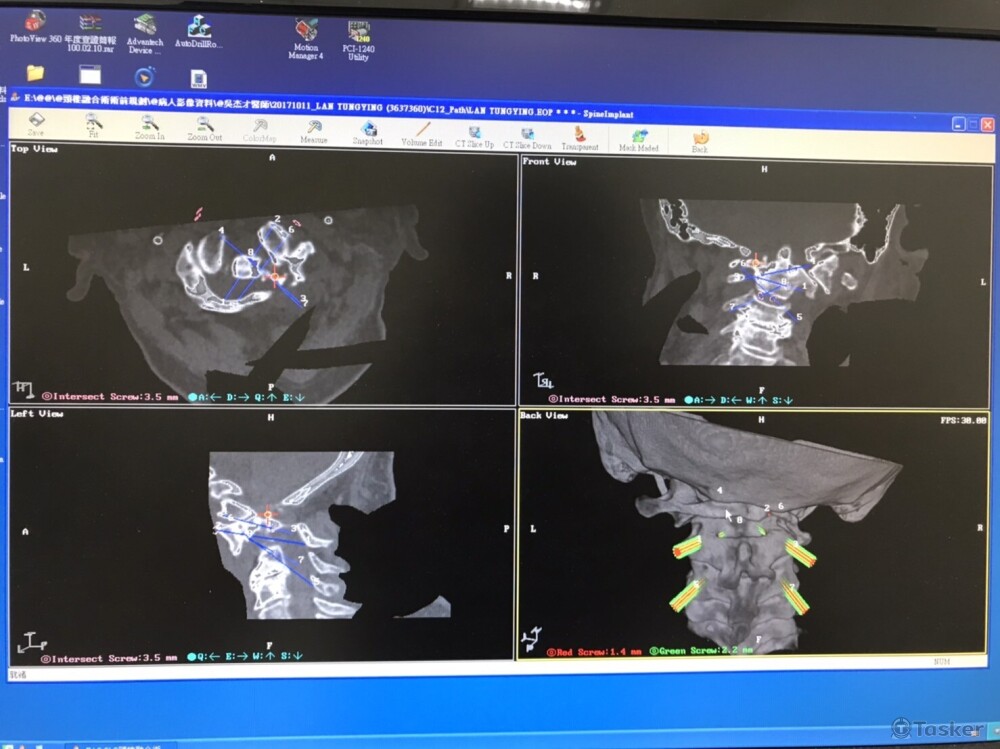

骨釘植入規畫系統-影像規畫介面

骨釘植入規畫系統-手術計畫